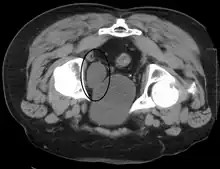

Investigations performed usually include collecting a sample of urine for an inspection for malignant cells under a microscope, called cytology, as well as medical imaging by a CT urogram or ultrasound.[29] If a concerning lesion is seen, a flexible camera may be inserted into the bladder, called cystoscopy, in order to view the lesion and take a biopsy, and a CT scan will be performed of other body parts (a CT scan of the chest, abdomen and pelvis) to look for additional metastatic lesions.[29]

Treatment depends on the cancer's stage. Cancer present only in the bladder may be removed surgically via cystoscopy; an injection of the chemotherapeutic mitomycin C may be performed at the same time.[29] Cancers that are high grade may be treated with an injection of the BCG vaccine into the bladder wall, and may require surgical removal if it does not resolve.[29] Cancer that is invading through the bladder wall may be managed by complete surgical removal of the bladder (radical cystectomy), with the ureters diverted into a segment of part of ileum connected to a stoma bag on the skin.[29] Prognosis can vary markedly depending on the cancer's stage and grade, with a better prognosis associated with tumours found only in the bladder, that are low grade, that do not invade through the bladder wall, and that is papillary in visual appearance.[29]

A number of investigations are used to examine the bladder. The investigations that are ordered will depend on the taking of a medical history and an examination. The examination may involve a medical practitioner feeling in the suprapubic area for tenderness or fullness that might indicate an inflamed or full bladder. Blood tests may be ordered that may indicate inflammation; for example a full blood count may demonstrate elevated white blood cells, or a C-reactive protein may be elevated in an infection.

Some forms of medical imaging exist to visualise the bladder. A bladder ultrasound may be conducted to view how much urine is within the bladder, indicating urinary retention. A urinary tract ultrasound, conducted by a more trained operator, may be conducted to view whether there are stones, tumours or sites of obstruction within the bladder and urinary tract. A CT scan may also be ordered.

A flexible internal camera, called a cystoscope, can be inserted to view the internal appearance of the bladder and take a biopsy if required.